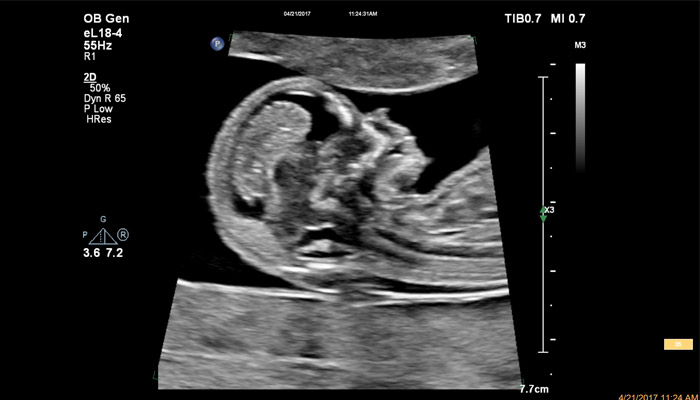

Начало новой жизни - это всегда особое время! Ультразвуковые решения Philips в области акушерства разработаны для того, чтобы позволить врачам сосредоточиться на здоровье каждой будущей мамы. Разработанные для обеспечения клиницистов дополнительной информацией ультразвуковые решения Philips позволяют получать не только детальную визуализацию анатомии плода уже в первом триместре, но и помогают оптимизировать рабочий процесс врача. Применение eL18-4 в I триместре беременности Сегодня ультразвуковая диагностика используется для выявления генетических аномалий, внутриутробных пороков, оценки жизнеспособности плода и определения срока беременности, как наиболее эффективный метод. Ультразвуковое исследование плода в первом триместре (до 13 недель 6 дней беременности включительно) является наиболее точным методом. В течение многих десятилетий трансвагинальный метод ультразвукового исследования был «золотым стандартом» диагностики в акушерстве. Сегодня линейный матричный датчик может стать альтернативой общепринятому трансвагинальному методу оценки состояния плода и репродуктивных органов женщины. Детальная анатомия плода и ранняя диагностика пороков в I триместре Ультразвуковое исследование является основным методом визуализации для оценки врожденных аномалий плода. Линейный матричный датчик eL18-4 позволяет получить детальную информацию об анатомии плода и выявить пороки на ранней стадии развития. Сверхширокополосная PureWave матрица датчика генерирует частоты в диапазоне 2-22 МГц, что формирует одинаково высокоинформативные, четкие изображения по всей глубине сканирования до 14 см.

Использование линейного матричного датчика eL18-4 при осмотре беременных в I триместре, особенно на ранних сроках, позволяет ограничиться трансабдоминальным сканированием вместо трансвагинального и при этом получить максимально полную диагностическую информацию. Отсутствие полостного исследования чрезвычайно важно для соблюдения принципа ALARA – использования минимальной необходимой мощности для безопасности пациента. Благодаря применению мультичастотного датчика с диапазоном от 2 до 22 МГц через переднюю брюшную стенку хорошо определяется эмбрион длиной 3 мм, что соответствует шестой неделе беременности. В конце I триместра с eL18-4 достаточно отчётливо визуализируется четырёхкамерный срез сердца, мочевой пузырь и сосуды пуповины, которые, как правило, определяются только при трансвагинальном сканировании.

Во II триместре беременности высокая разрешающая способность eL18-4 позволяет детально изучить структуру органов и тканей и увидеть многие нюансы, которые при работе другими датчиками не обнаруживались или становились очевидны в более поздние сроки. Например, у 19-недельного плода визуализируется перегородка носа, мышцы языка, диафрагма между грудной и брюшной полостью, на 20-й неделе чётко определяются оболочки спинного мозга и уретра, а на 24-й – хорошо дифференцируются корень лёгкого, борозды и извилины мозжечка и многие другие структуры.